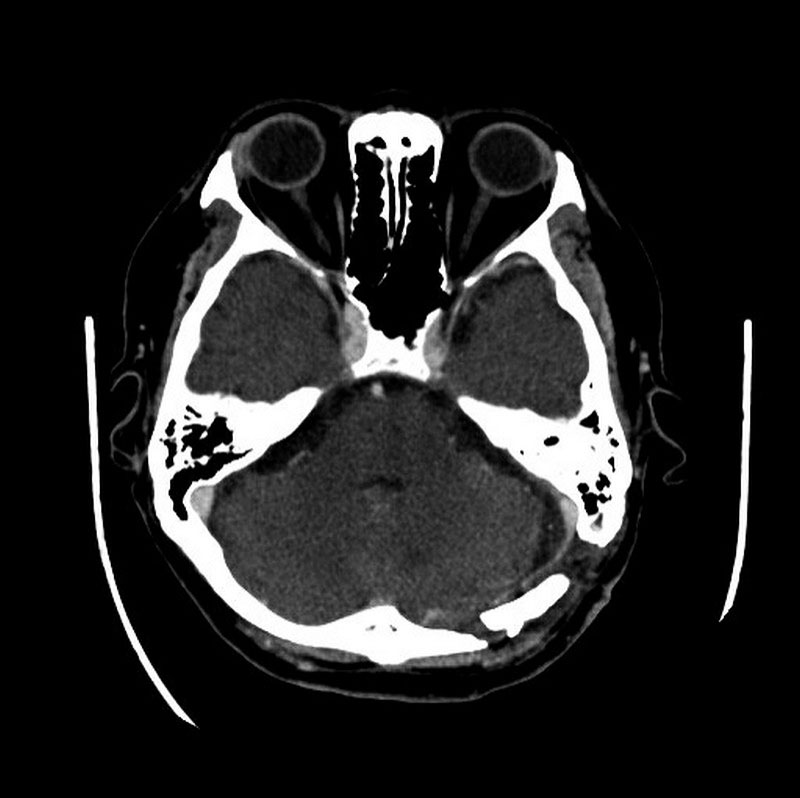

左為手術前的核磁共振掃描,顯示紅圈處有一個小於兩公分大的腫瘤;右為術後電腦斷層,確認腫瘤已完整取出。圖/台北慈院提供